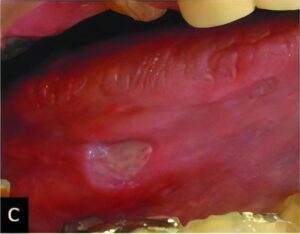

悪性腫瘍

口腔内に発生する悪性腫瘍では、扁平上皮癌という口腔内の粘膜から発生する癌が最も多いのが特徴です。その他には、唾液腺から発生するものや骨肉腫などの内部の組織から発生する悪性腫瘍もあります。

悪性腫瘍を歯周病や口内炎、義歯による傷などと思い込み、長期間放置し、腫瘍が大きくなてから歯科医院を受診するケースが多いようです。口腔内の悪性腫瘍だけに限定される話ではありませんが、早期発見・早期治療が重要です。